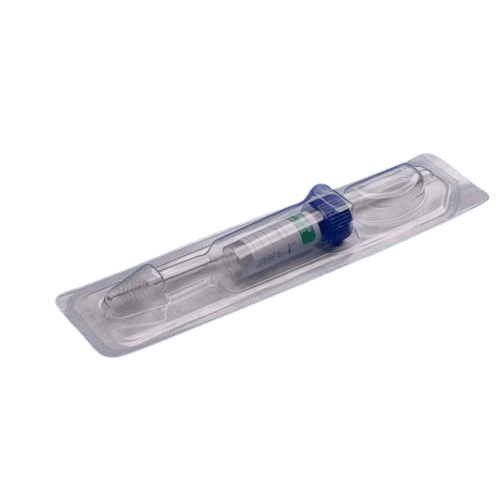

Humasis Early precision pregnancy diagnostic kit with results within 15 minutes after blood draw. Detects pregnancy earlier than urine tests for planned pregnancies and prenatal care.